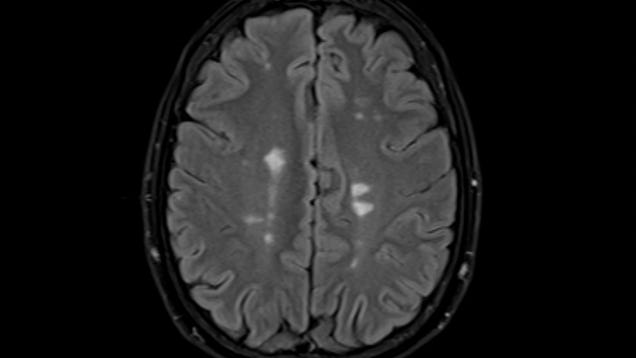

Early clinical data is showing promise for an experimental treatment tackling multiple sclerosis. The treatment, which targets a virus closely linked to MS called Epstein-Barr virus, was found to be safe and possibly effective at halting the progression of symptoms in some patients. But it will take much more data to…

Source: Gizmodo – Promising Data Suggests New Multiple Sclerosis Therapy Could Halt or Reverse Symptoms